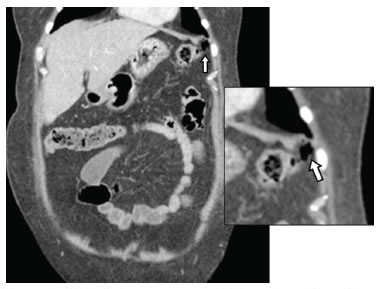

En las tres pacientes, la TC abdominal con contraste mostró el neumoperitoneo pericólico o localizado a menos de 5 cm del asa inflamada sin aire distante (figuras 2 y 3); dos presentaron divertículos en el ángulo esplénico, colon descendente y sigmoide, y una en el colon sigmoide únicamente.

La diverticulitis en las tres pacientes fue de grado Ia por la presencia de inflamación pericólica y la clasificación de Hinchey modificada por Wasvary, y grave por la presencia de aire externo a la luz intestinal en la TC y la clasificación de Ambrosetti (tabla 1) 5.